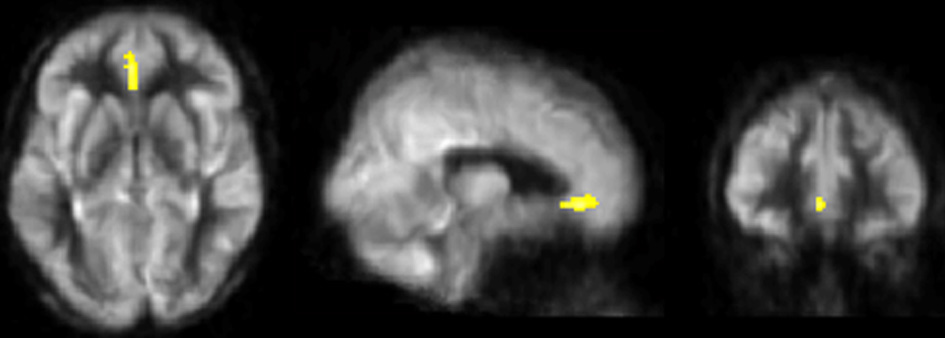

Figure 2 shows the whole-brain results from the VBA. The physical training group showed an increase in resting-state blood flow from T1 to T3 in bilateral anterior cingulate (ACC) compared to the control group (FWE corrected p < 0.05). Table 4 summarizes ACC finding.

Figure 2

Results of CBF voxel based comparison superimposed on an average CBF map of all participants. Anterior cingulate cortex's CBF increased from T1 to T3 in the physical training group (shown in yellow) compared to the control group, p < 0.05 (FWE corrected) and k ≥ 664 mm3.

| L/R anterior cingulate | 32 | 696 | 0 | 34 | −8 | 3.90 |